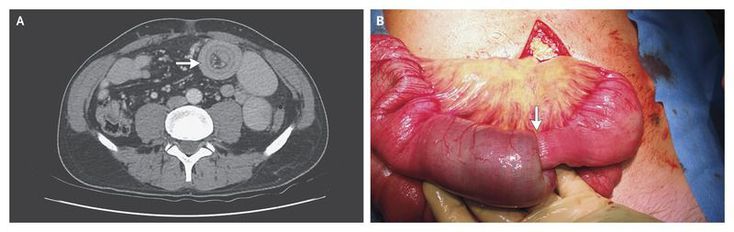

A previously healthy 52-year-old man with epigastric pain and nausea was transferred to our hospital after computed tomography (CT) of the abdomen revealed findings suggestive of enteroenteric intussusception. He was treated successfully with conservative therapy. Three days after his discharge, while awaiting the results of further diagnostic studies, he presented with similar symptoms. On physical examination, he appeared to be moderately ill, with diffuse abdominal discomfort; there were no clinical signs of peritonitis. All laboratory tests were unrevealing. CT of the abdomen, which was performed on readmission, showed dilated small-bowel loops and a “target sign” (Panel A, arrow), findings characteristic of intussusception, without evidence of a lead point. A laparotomy was performed, and the findings confirmed the suspected diagnosis of jejunojejunal intussusception. There was ischemic discoloration of the small bowel, and an intraluminal tumor was felt at the lead point of the intussusception (Panel B, arrow). A 15-cm segment of the proximal jejunum was resected, and a side-to-side anastomosis was performed. Pathological examination of the specimen revealed a 5.5-cm T2N0 adenocarcinoma, with clear resection margins. The postoperative course was unremarkable, and the patient was doing well at an 8-month follow-up visit.